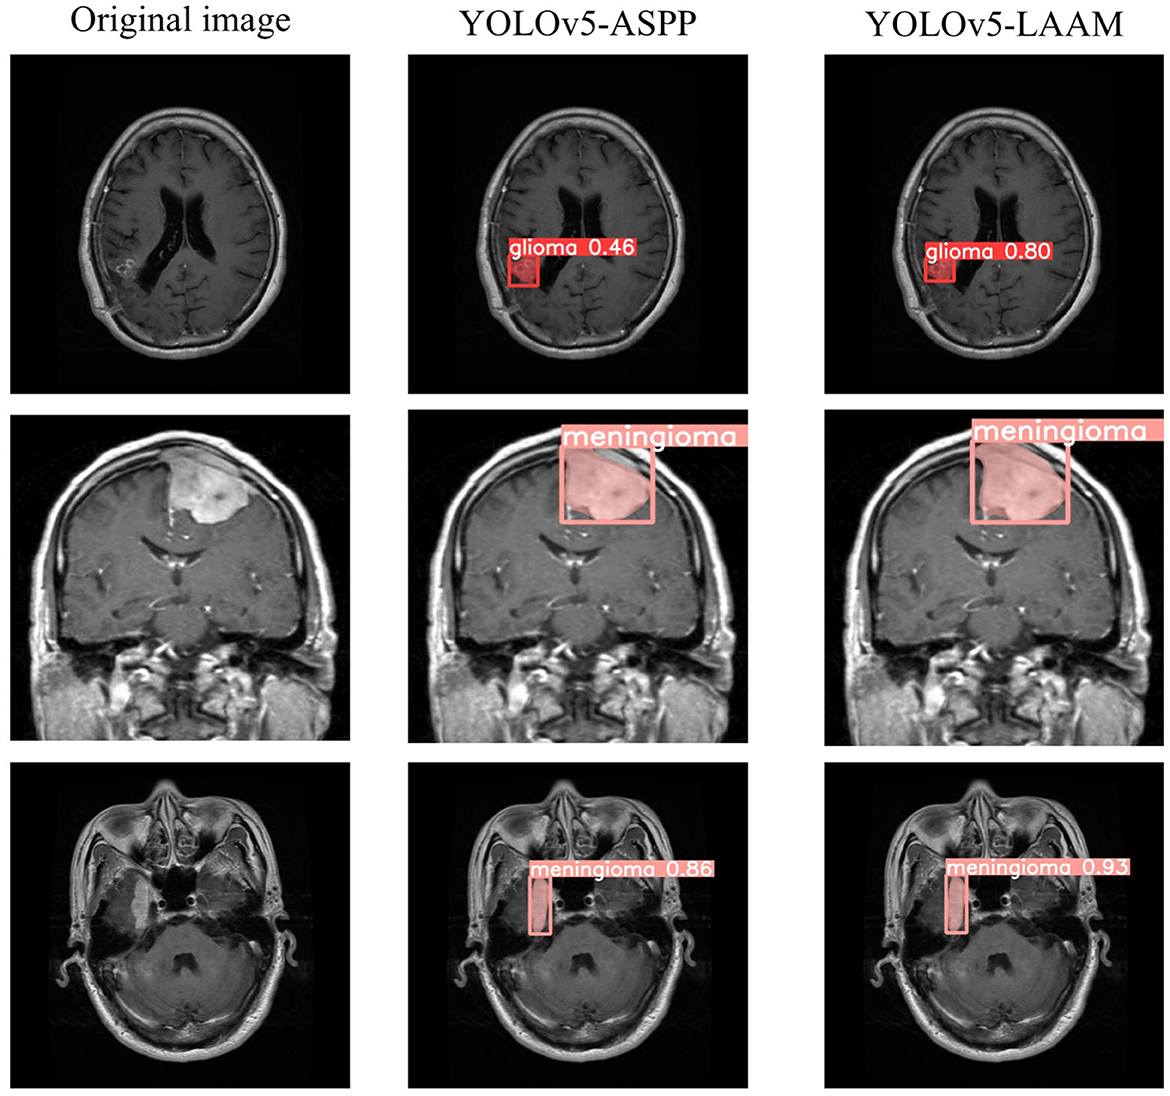

As shown in Tables 7, 8, on the internal test set, YOLOv5s-LAAM outperformed YOLOv5s-ASPP in both overall performance (mAP@50: 0.833) and recall rate (0.824), compared to the latter's scores (0.826 and 0.784, respectively). This indicates its superior lesion coverage capability and improved control over missed detections. Although its precision (0.748) on the external test set was lower than that of the ASPP variant (0.82), LAAM still maintained a higher recall rate (0.741). Furthermore, as illustrated in Figures 9, 10, it provided more complete and accurate localization and delineation of tumor regions.

Figure 9

Test results of YOLOv5-ASPP and YOLOv5-LAAM on the internal test set.

Figure 10

Test results of YOLOv5-ASPP and YOLOv5-LAAM on the external test set.